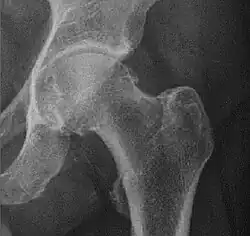

![Figure 5 (c). Protrusio acetabuli.[3]](./_assets_/X-ray_of_protrusio_acetabuli.jpg)